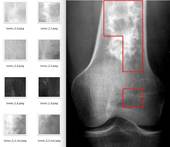

Bone Tumor Precision

Precision Diagnosis of Bone Tumors

Using deep learning and bayesian network for generating ddx of bone tumors on xray.